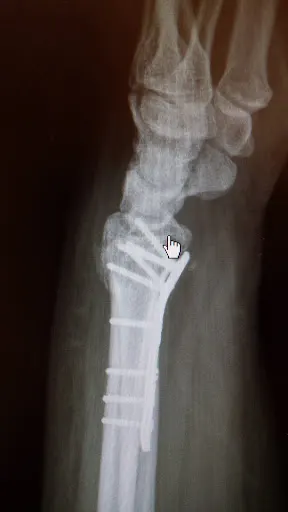

W Ciechanowie, przy ulicy Małgorzackiej 9, prowadzi praktykę lek. med. Tomasz Poboży, specjalista w dziedzinie ortopedii. Pacjenci mogą skorzystać u niego z badań USG stawów oraz leczenia operacyjnego, w tym skomplikowanych przypadków wymagających interwencji chirurgicznej. Gabinet znajduje się pod adresem 06-400 Ciechanów i stanowi wygodną opcję dla mieszkańców regionu szukających fachowej pomocy ortopedycznej. Opinie klientów podkreślają profesjonalne i rzeczowe podejście doktora. Jedna z osób relacjonuje, że dzięki szybkiej diagnozie udało się zorganizować termin operacji dla bliskiego, co przyniosło ulgę całej rodzinie. Inni pacjenci doceniają specjalistyczną wiedzę w zakresie stawu barkowego – przykładowo, w przypadku złożonego złamania ramienia wymagającego wymiany barku. Te doświadczenia potwierdzają skuteczność i empatię w codziennej praktyce. Na Google lek. med. Tomasz Poboży cieszy się doskonałą oceną 5.0/5 na podstawie trzech opinii, co świadczy o wysokim poziomie zaufania wśród pacjentów. Warto rozważyć wizytę w tym sprawdzonym gabinecie ortopedycznym w Ciechanowie. (Słowa: 198)